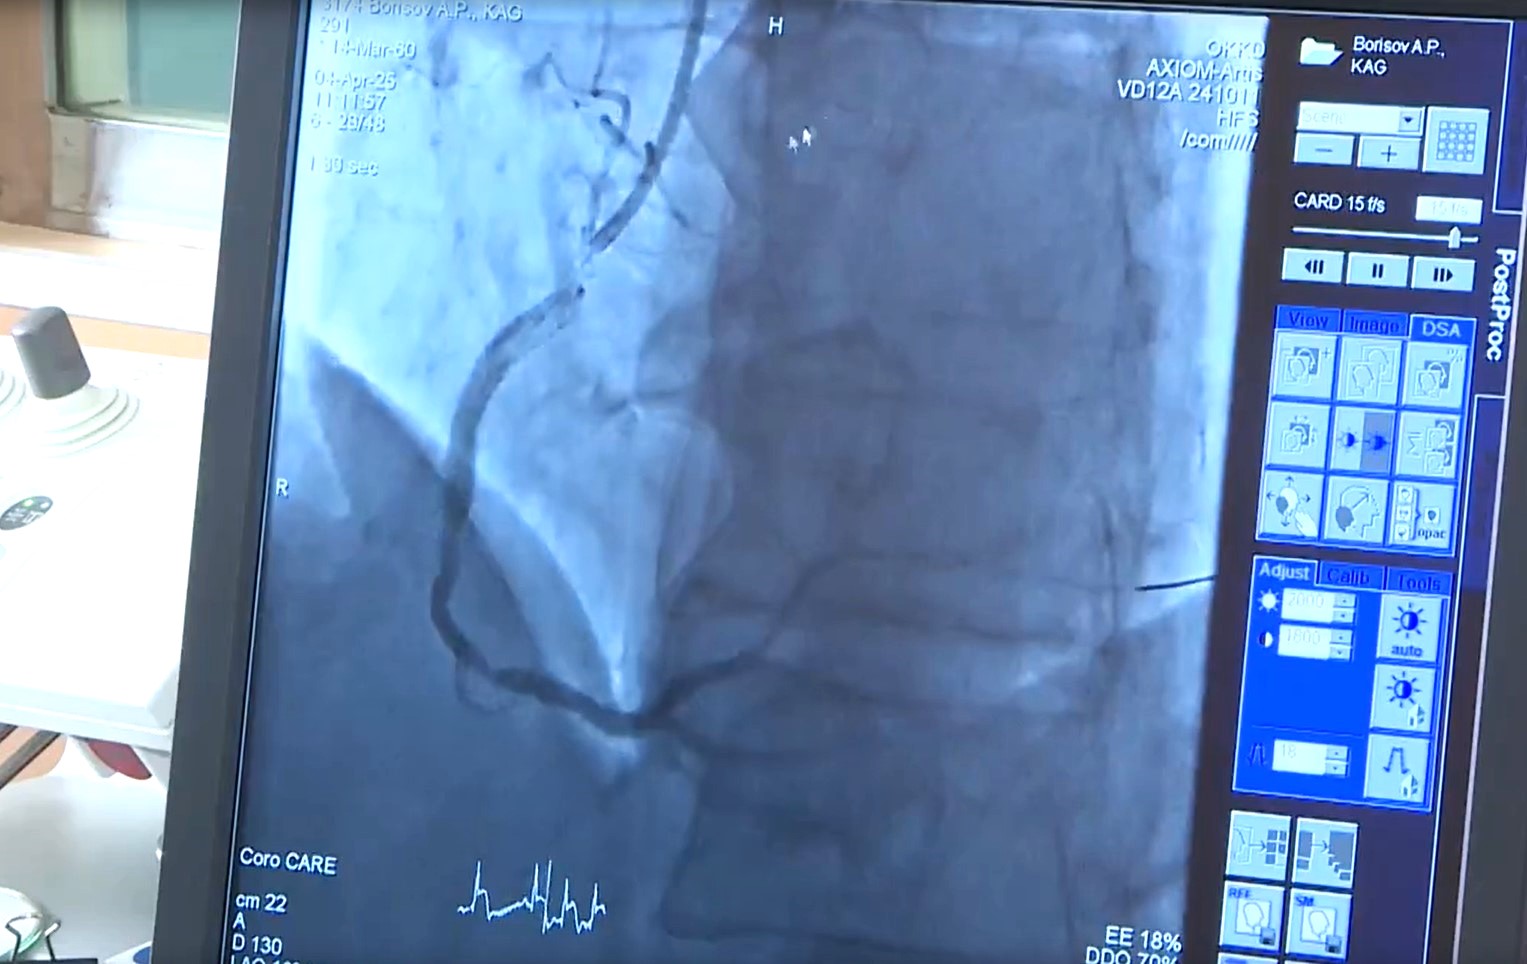

Врач-кардиолог диагностировал острый инфаркт. Пациента экстренно госпитализировали. Для оценки состояния сосудов была проведена коронарная ангиография.